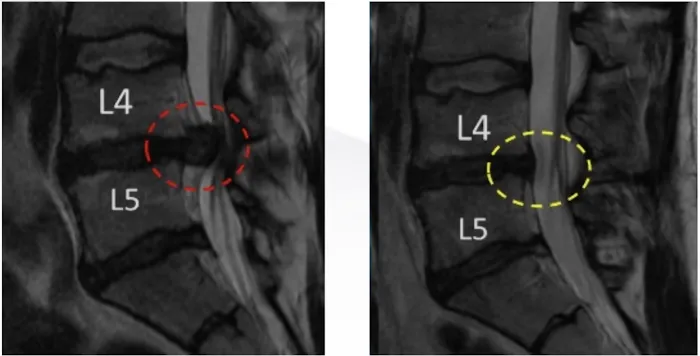

- Spinal Decompression Therapy: This is the core service and specialty of the practice. This non-invasive, non-surgical treatment is designed to gently stretch the spine, relieving pressure on the spinal discs and nerves. It is highly effective for conditions like herniated discs and sciatica, helping to reduce pain and improve function.

- Herniated Disc Treatment: The practice focuses on addressing the root cause of herniated disc pain. Through spinal decompression and other related therapies, they work to alleviate pressure on the affected discs, which can lead to a significant reduction in pain and a return to normal activities.

- Sciatica Relief: Sciatica, a painful condition caused by compression of the sciatic nerve, is a primary concern for many patients. The practice uses targeted treatments to relieve this compression, leading to major improvements in pain and mobility, as highlighted in patient reviews.